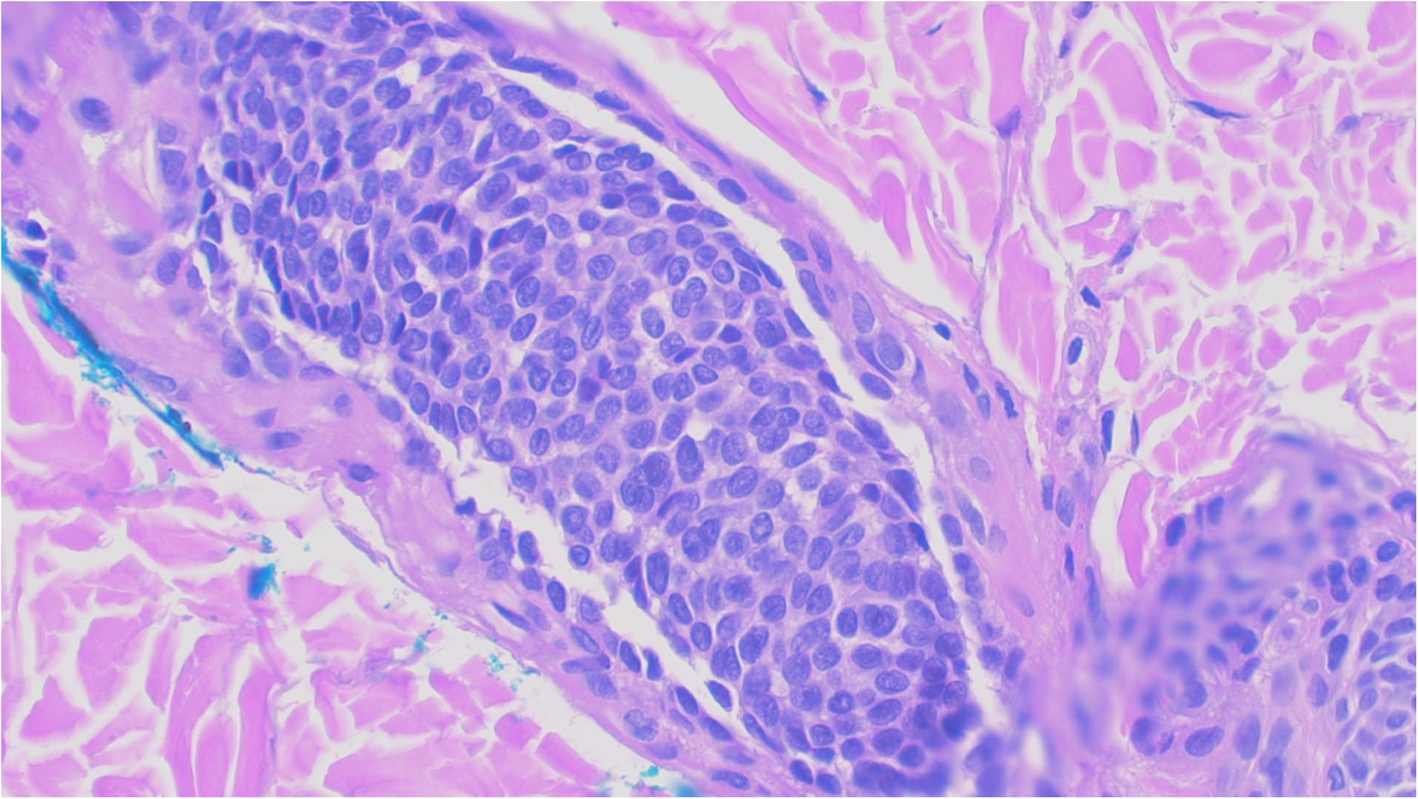

Fig. 11From: Interesting overlooked findings in melanocytic neviSuspicious for vascular invasion Hematoxylin and eosin 400XBack to article page